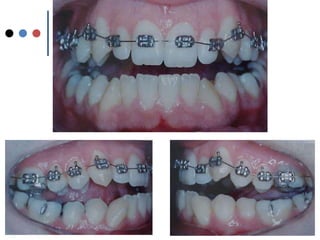

O documento apresenta registros odontológicos de um paciente ao longo de vários anos, incluindo panorâmicas iniciais e subsequentes, remodelações de arcadas dentárias superiores e inferiores ao longo de 7 meses, vedamentos labiais e registros de máxima intercuspidação e guias caninas nas datas listadas.